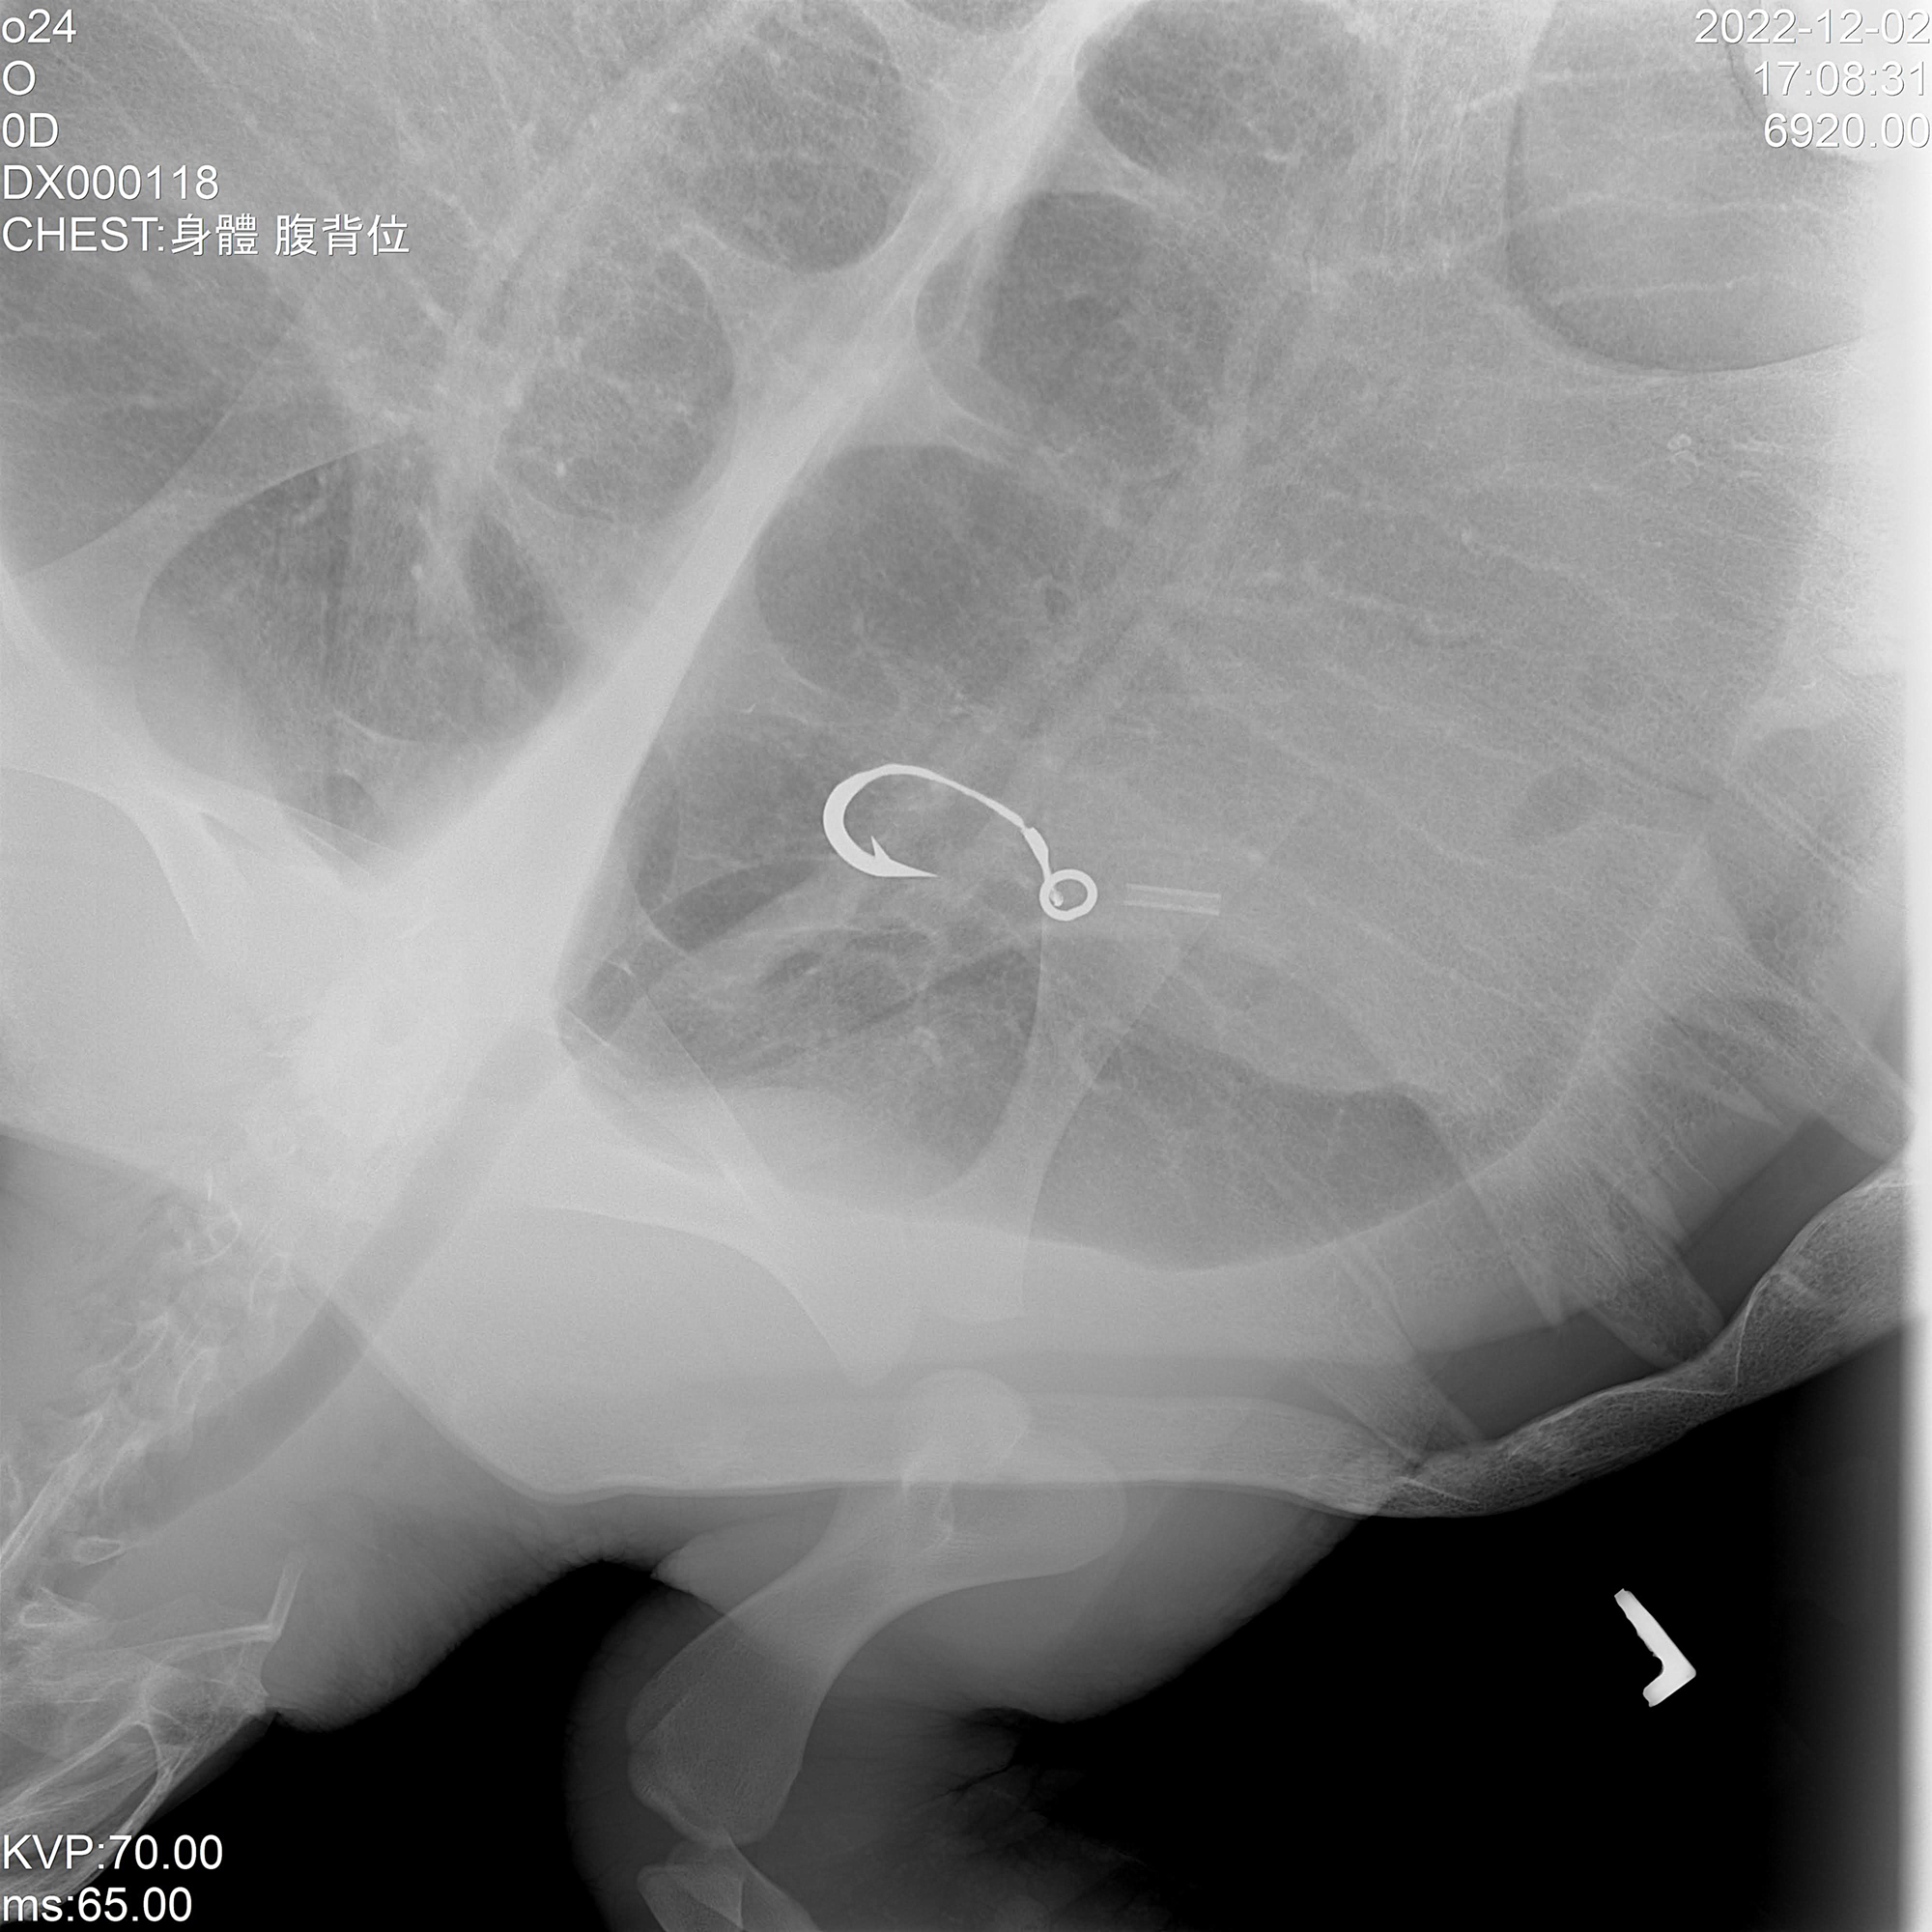

收容中心另一頭,重達數十公斤的113-04被中華鯨豚協會獸醫團隊以保定姿態,暫時安置在軟墊上,接著以都卜勒檢查脈搏,以及進行測量背甲和腹甲長度、檢查有無明顯外傷,還有抽血作業等健康檢查項目。

中華鯨豚協會野動救援組獸醫師陳毓蓉補充,尚未把海龜帶出水池前,他們也會觀察其游泳姿態、遇見人的反應等行為,因為海龜每個舉動都是判斷病情的重要依據。

每隻送到收容中心的海龜,皆需經過獸醫縝密檢查。(國立海洋生物博物館提供)